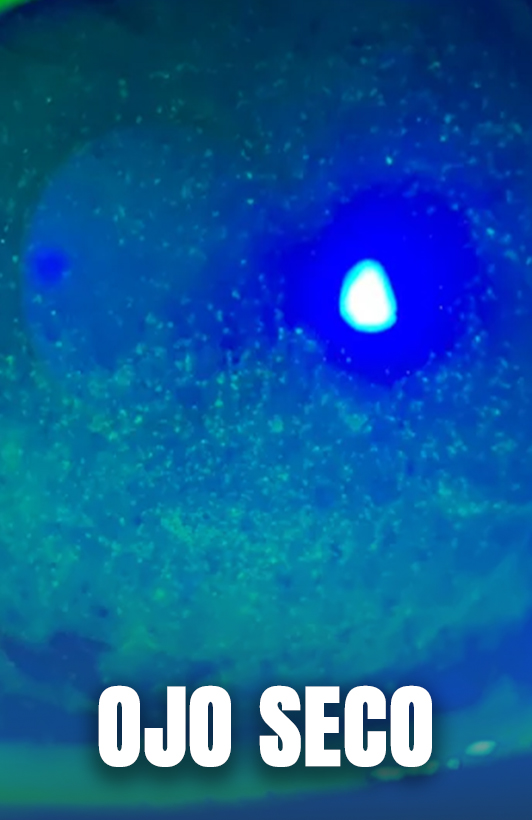

Ojo seco